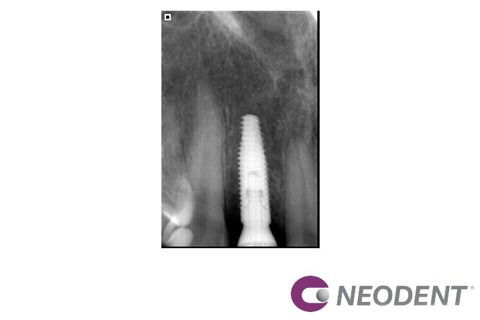

Paciente L.R.S, 53 anos, procurou o consultório devido à agenesia dos dois incisivos laterais superiores permanentes. A paciente possuía restaurações em resina composta nos laterais decíduos para reanatomizar o formato (Fotografia 1). O elemento 62 havia esfoliado e foi reabilitado através de uma ponte provisória adesiva envolvendo os dentes adjacentes. Após avaliação, decidiu-se realizar a instalação de dois implantes de maneira guiada. Através de tomografia, o caso foi planejado e a posição dos implantes foi determinada virtualmente no software coDiagnostiX® (Fotografia 2). A exodontia do elemento 52 foi realizada (Fotografias 3 e 4) seguida da instalação dos implantes Neodent Helix GM Aqua 3,5x13mm com guia restritivo (Fotografias 5 e 6). Utilizou-se componentes protéticos diferentes, munhão anatômico para lateral 1,5 de altura no elemento 12 (Fotografia 7) e munhão universal 3,3x4x2,5 de altura no elemento 22 (Fotografia 8). Os dois componentes foram instalados com torque final de 20N seguindo o conceito One abutment one time1 e as provisórias foram instaladas no mesmo dia.Aspecto radiográfico e clínico após 2 meses (Fotografias 9,10 e 11). Além de aumentar a previsibilidade do resultado, a utilização do método guiado melhora a cicatrização, já que a instalação é realizada sem incisões.